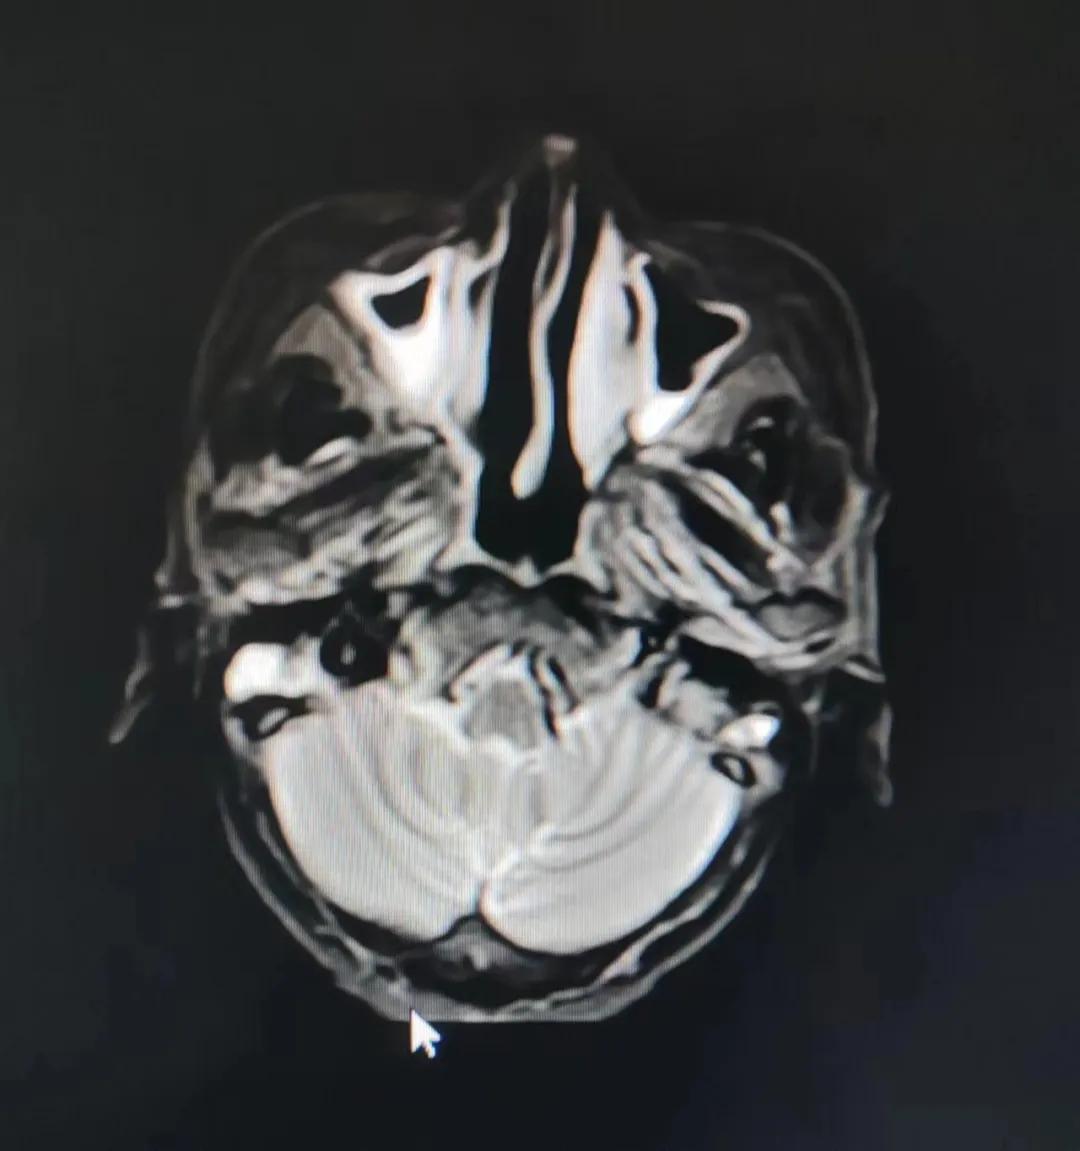

治療前

老人因鼻部腫物堵塞鼻腔并且侵犯鼻咽導(dǎo)致鼻塞、疼痛、吞咽困難,身心都備受煎熬,趙亮主任在詢(xún)問(wèn)其病史期間幾度落淚。趙亮主任向患者及家屬解釋說(shuō):“現(xiàn)代放療比過(guò)去的傳統(tǒng)放療設(shè)備先進(jìn),技術(shù)不斷提升,能對(duì)腫瘤區(qū)域的照射劑量進(jìn)行優(yōu)化,做到準(zhǔn)確定位、精準(zhǔn)照射,同時(shí),最大限度地降低正常組織的受量,對(duì)全身情況影響很小。”

考慮到患者年齡較大、體質(zhì)差,手術(shù)難度大,且常規(guī)的放射治療難以保護(hù)患者晶體造成患者雙眼視力損傷,放療團(tuán)隊(duì)以最快的速度制定了精準(zhǔn)放射治療方案并開(kāi)始為其實(shí)施治療。僅僅數(shù)日后,老人腫塊出血即得到控制,腫塊明顯縮小,放療20次后腫塊迅速縮??!